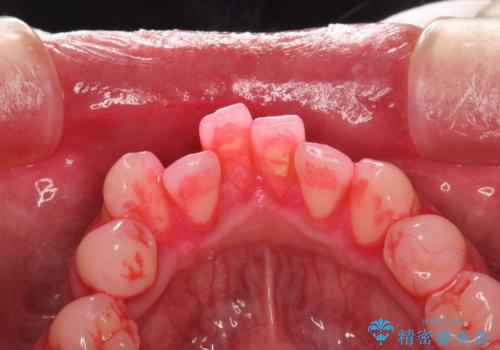

- 治療計画

- 歯科でのクリーニングがかなり久しぶりで口臭も気になるとのことで来院されました。PMTCの60分コースで、染め出し・ブラッシング指導・クリーニングを行いました。

適切な歯磨き方法を習得するには、染め出しを行い、磨き残しを把握していくことがポイントです。

磨けているよう、磨いているつもりでも、汚れが残ってしまうと、毎日の歯磨き時間が無駄になってしまうこともあります。効率的に歯磨きを行い、磨き残しを減らせるように、歯科衛生士による専門的な指導を行います。